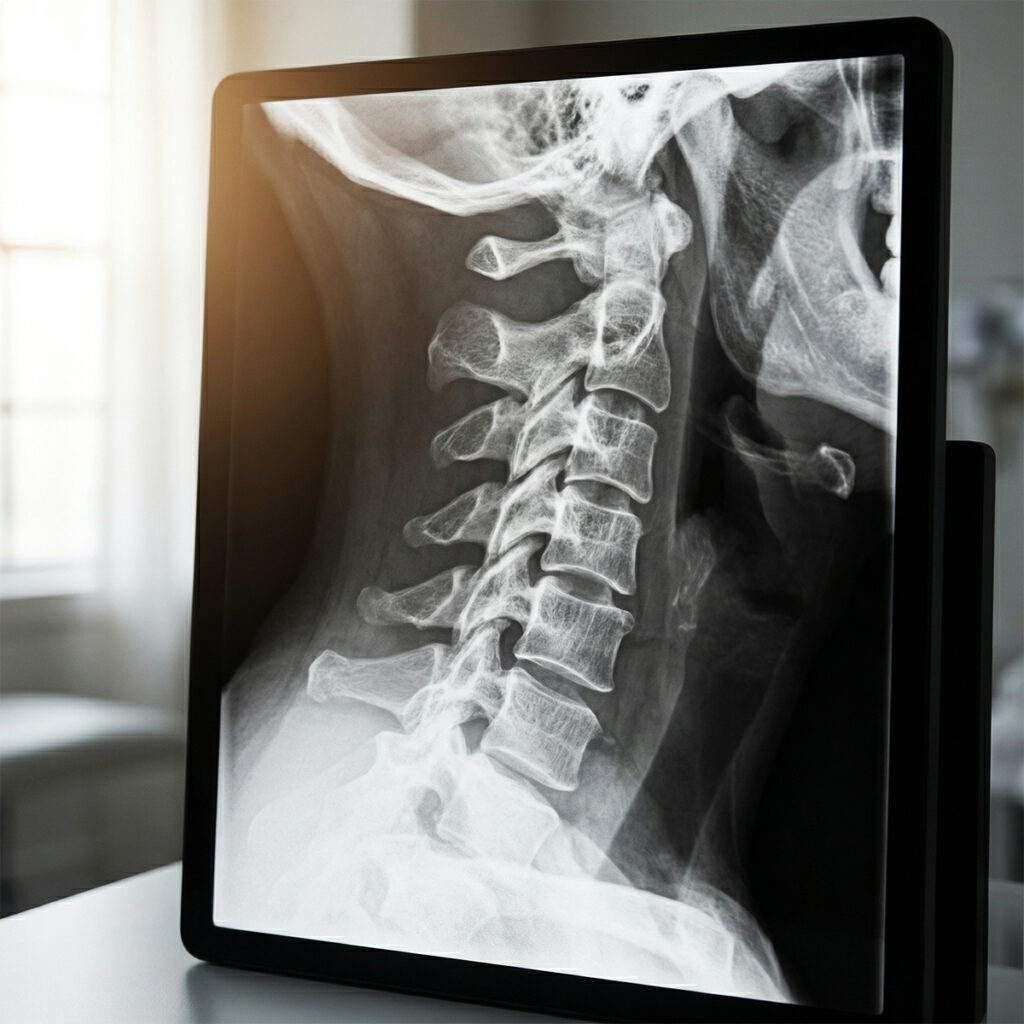

우리 목뼈는 본래 완만한 ‘C자형’ 곡선을 유지하며 머리의 무게를 분산시키는 역할을 합니다.

하지만 고개를 앞으로 숙이는 자세가 지속되면 이 곡선이 무너지며 일자 형태, 혹은 역 C자 형태로 변형되는데 이것이 바로 거북목입니다.

성인의 머리 무게는 보통 5kg 내외지만, 고개가 1cm씩 앞으로 나올 때마다 목이 받는 하중은 2~3kg씩 기하급수적으로 늘어납니다.

거북목이 심화되면 목 신경이 최대 15kg 이상의 압박을 받게 되며, 이는 어깨 결림, 손 저림, 안구 건조증까지 유발합니다.